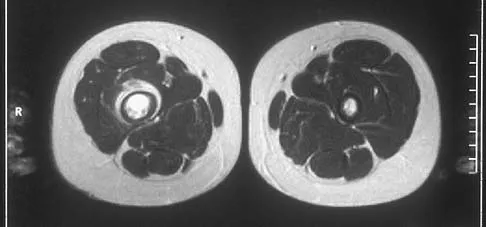

A 37-year-old woman has had intermittent paresthesias and numbness in the plantar foot for the past 6 months. She reports that the symptoms are worse with activity, and the paresthesias are beginning to awaken her at night. MRI scans are shown in Figures 6a and 6b. What is the most likely diagnosis?

Explanation

The symptoms are consistent with tarsal tunnel syndrome. Ganglion cysts are a well-known cause of tarsal tunnel syndrome. The MRI scans show a high intensity, well-circumscribed mass in the tarsal tunnel that is consistent with a fluid-filled cyst. Patients usually respond well to excision of the ganglion and resolution of the tarsal tunnel symptoms. The surrounding fat is a different signal intensity on the MRI scans, which rules out a lipoma. Synovial cell sarcoma has a heterogeneous appearance on an MRI scan. Metastatic tumors are most commonly found in the osseous structures of the foot, not the soft tissues. Rozbruch SR, Chang V, Bohne WH, et al: Ganglion cysts of the lower extremity: An analysis of 54 cases and review of the literature. Orthopedics 1998;21:141-148. Llauger J, Palmer J, Monill JM, et al: MR imaging of benign soft-tissue masses of the foot and ankle. Radiographics 1998;18:1481-1498.